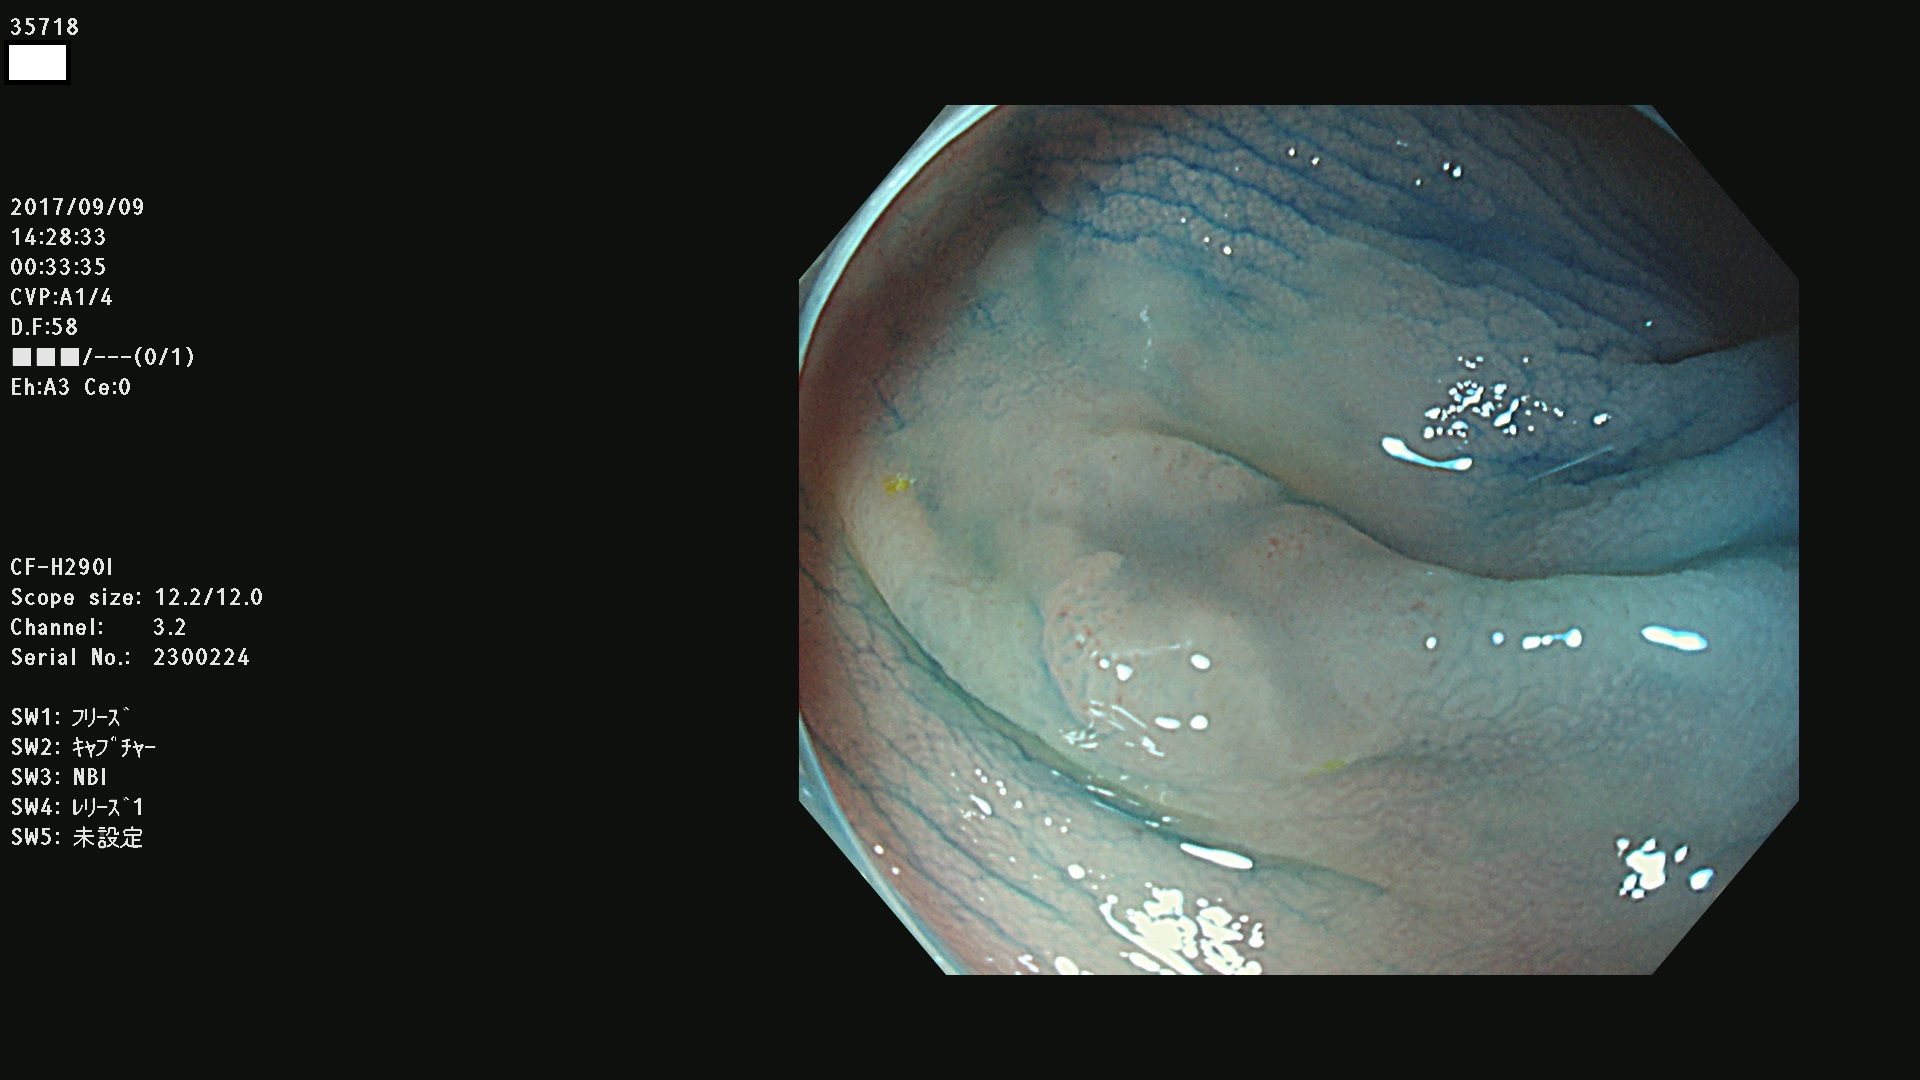

35700 35701 35704 35706 35707 35708 35709 35711(SSA/Pのみ) 35715 35716 35717 35718 35720(SSA/Pのみ) 35722 3576(SSA/Pのみ) 35730 35732 35734(SSA/Pのみ) 35736(SSA/Pのみ) 35741 35742 35743 35744 35746 35748 35749(SSA/Pのみ)35755 35757 35760 35761 35762 35763 35764 35766 35767 35770 35772(SSA/Pのみ) 35773 35781 35783 35785 35786 35787 35788 35791 35795 35796 35797 35798 35799

発見困難で危険性の高い平坦型病変(上記100名より抽出)